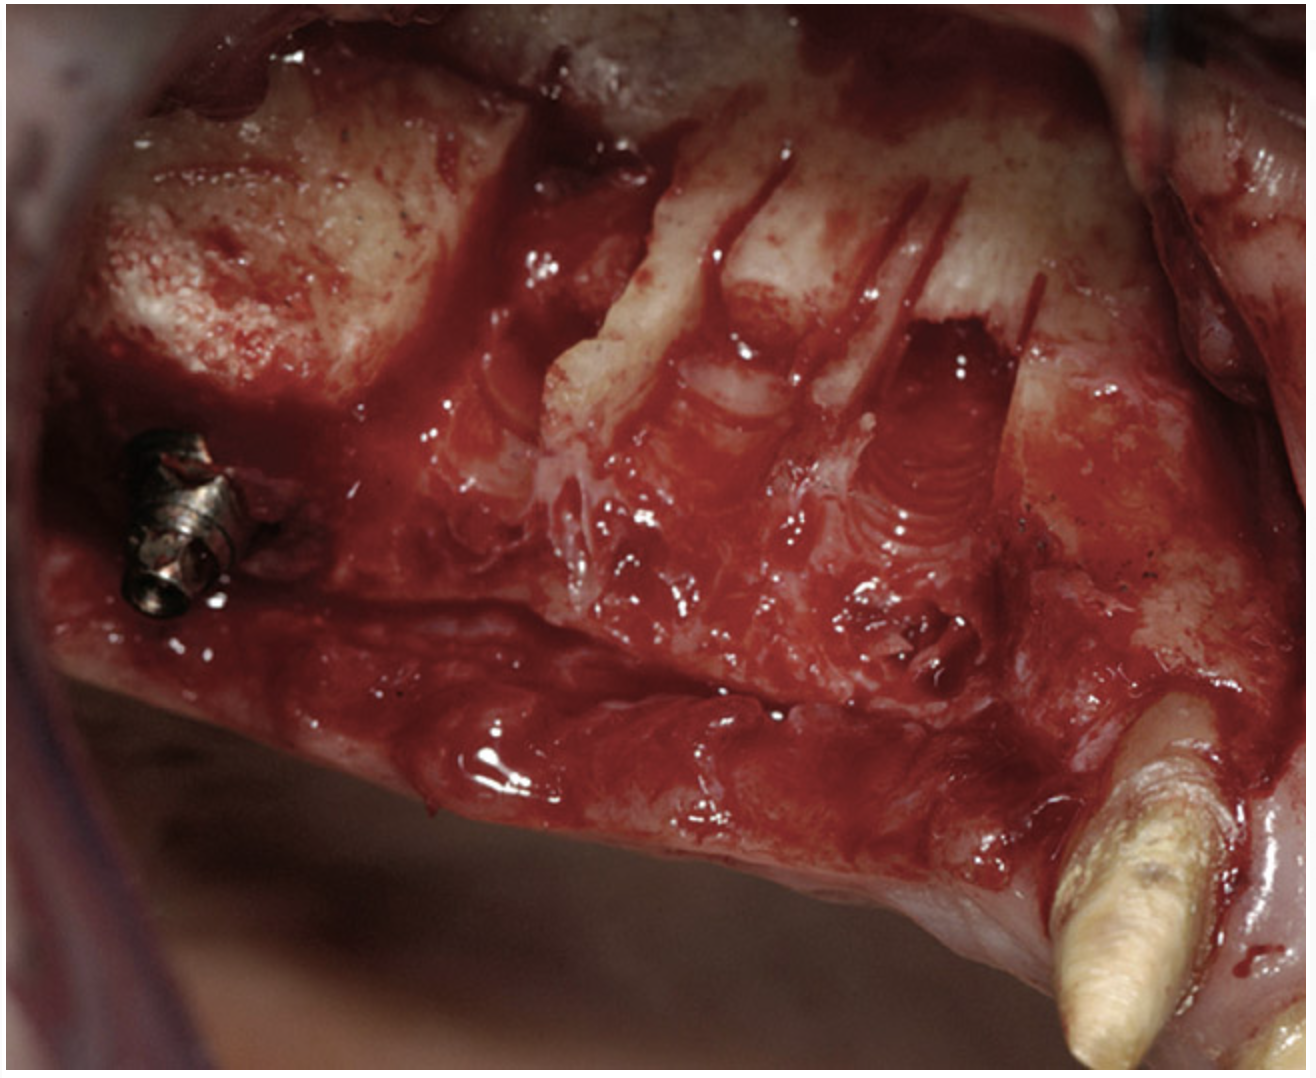

A 72-year-old man was referred for removal of failing maxillary right posterior implants (Figure 19). The treatment plan included removal of three implants with simultaneous bone augmentation and replacement implants for implant-supported fixed bridgework. Implant removal and bone grafting with rhPDGF (Gem 21®, Osteohealth, www.osteohealth.com) and allograft (MinerOss) and xenograft (BioOss®, Geistlick, www.geistlickonline.com) were used along with titanium mesh for space maintenance (Figure 20, Figure 21 and Figure 22). Six months later, mesh removal revealed type I bone allowing for placement of three implants (Figure 23 and Figure 24).

Figure 19  Failing implants in the right posterior maxilla.

Figure 19

Figure 20  Removal of the failing implants.

Figure 20

Figure 21  Bone grafting with rhPDGF, allograft, and xenograft.

Figure 21

Figure 22  Titanium mesh fixation.

Figure 22